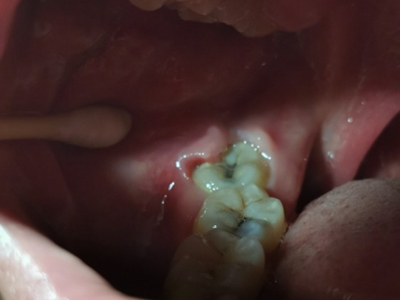

牙龈

肿

智齿冠周炎左侧下面智齿牙龈肿了图

智齿冠周炎患者左侧下面智齿处的牙龈发白,中间有牙尖冒出,周围黏膜肿胀,患者有明显的疼痛感。患者可遵医嘱口服消炎药物,炎症消除后可到医院牙科进行拔除治疗。